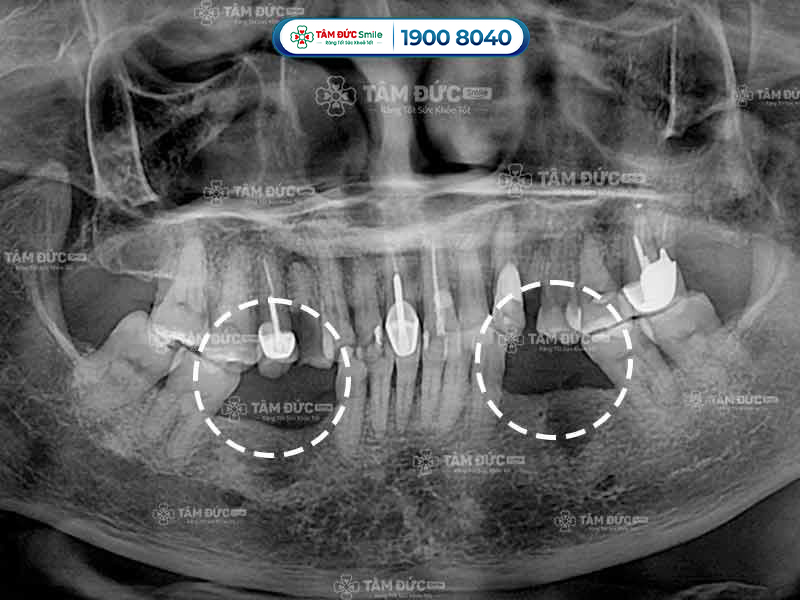

10.2. Bước 2 - Chụp phim CT Cone Beam và làm các xét nghiệm

Ngoài chụp phim CT, Quý khách còn được làm 1 số xét nghiệm cần thiết để đánh giá sức khỏe có đủ điều kiện trồng răng Implant hay không. Khi có đủ các kết quả kiểm tra, bác sĩ bắt đầu xây dựng phác đồ điều trị phù hợp.

- Kiểm tra chất lượng xương hàm trước khi trồng răng bằng cách chụp phim CT.

Trụ Implant kém chất lượng sẽ nhanh chóng bị cơ thể đào thải ra ngoài, làm Quý khách bị chảy máu chân răng hoặc viêm nướu. Kết quả chụp phim X-Quang cho thấy xương không bám vào trụ Implant, lúc này Quý khách cần phải trồng răng lại từ đầu.